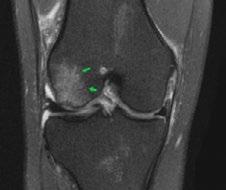

Issuu converts static files into: digital portfolios, online yearbooks, online catalogs, digital photo albums and more. Sign up and create your flipbook.